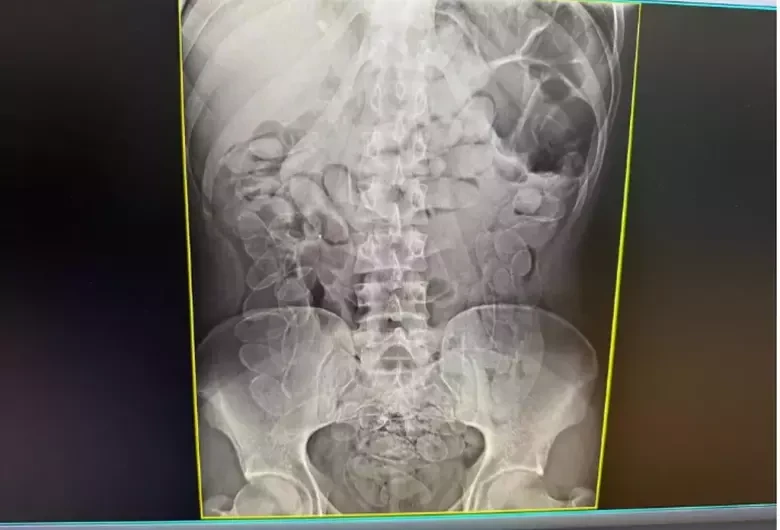

Ainda segundo o boletim de ocorrência, a mulher afirmou ter ingerido as cápsulas em território boliviano há cerca de sete dias e que permaneceu com o material no organismo durante todo esse período. Um exame de raio X da região abdominal revelou múltiplos invólucros no estômago.